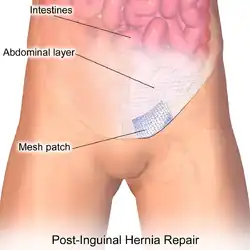

Muscle reinforcement techniques often involve synthetic materials (a mesh prosthesis).[41] The mesh is placed either over the defect (anterior repair) or under the defect (posterior repair). At times staples are used to keep the mesh in place. These mesh repair methods are often called "tension free" repairs because, unlike some suture methods (e.g., Shouldice), muscle is not pulled together under tension. However, this widely used terminology is misleading, as there are many tension-free suture methods that do not use mesh (e.g., Desarda, Guarnieri, Lipton-Estrin, etc.).